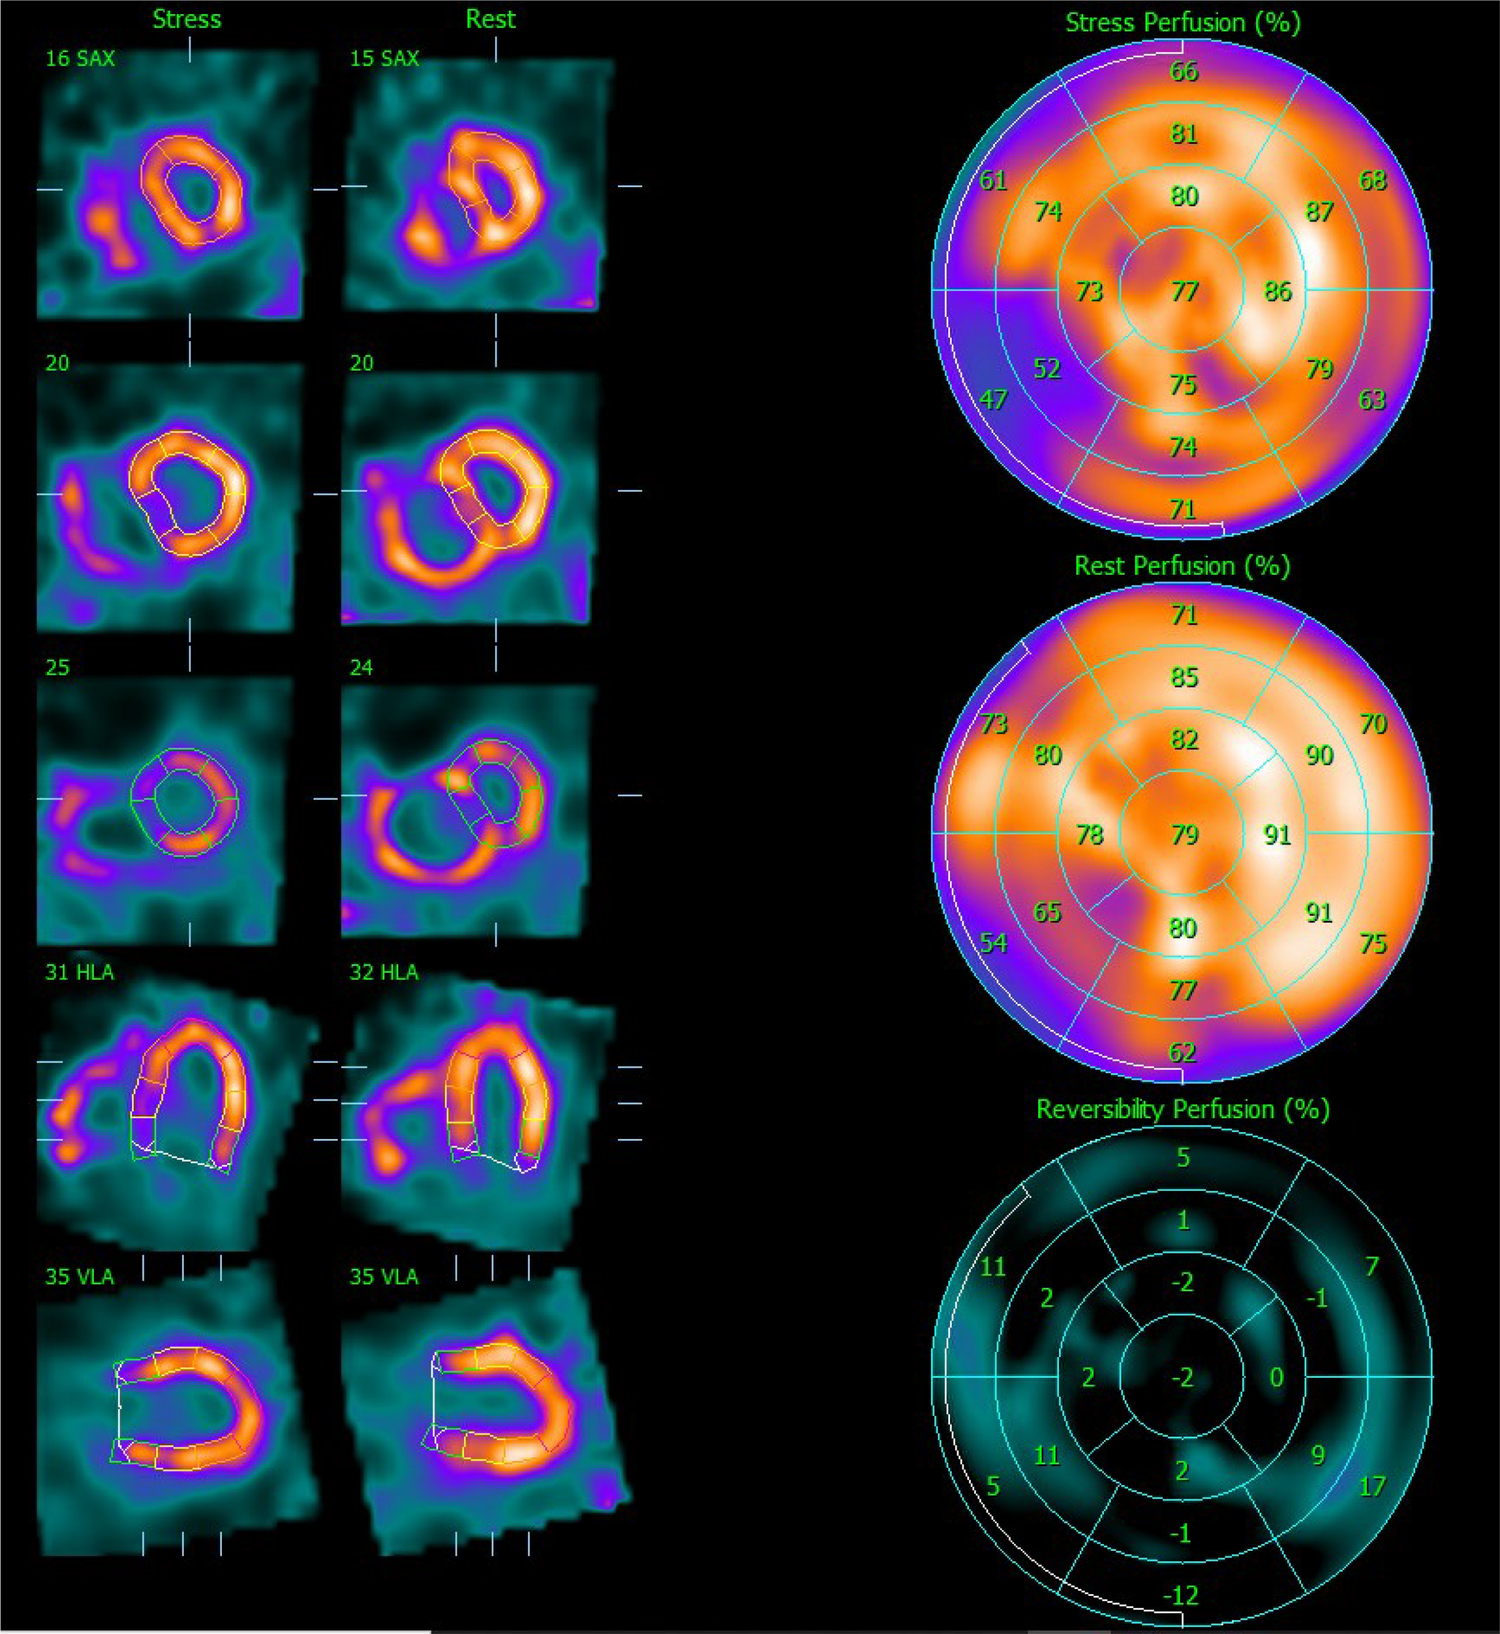

Figure 2

Myocardial perfusion SPECT images after stress and at rest. On the left side, the representation of the LV after stress and at rest is realigned along the three standard cardiac planes (short axis, vertical long axis, and horizontal long axis). On the right side, polar maps (stress, rest, and reversibility) illustrating the [99mTc]Tc-Tetrofosmin uptake interpreted as LV perfusion assessed semi-quantitatively using the percent of the uptake on the 17-segment scheme. SPECT, single photon emission computer tomography; LV, left ventricle.

Stress LV perfusion images showed a moderate perfusion defect in the mid-basal inferoseptal wall and a small perfusion defect in the basal segment of the inferolateral wall (SSS 5). At rest, we could observe a recovery of both perfusion defects as well as diffuse improvement of the LV perfusion (SRS 0), with an SDS of 5 (Figure 2). Gated acquisitions demonstrated normal LV function (LVEF > 60%), EDV, and ESV in both studies. No significant abnormalities were noted in LV wall motion and thickening analysis post-stress or at rest. Notably, the SPECT images displayed a non-typical finding—a heterogeneous and significantly enhanced tracer uptake in the RV wall, indicating increased vascularization and hypertrophy of the severely dilated RV. Additionally, the flattening of the interventricular septum resulting in a D-shaped LV suggests the presence of RV overload (Figure 3).